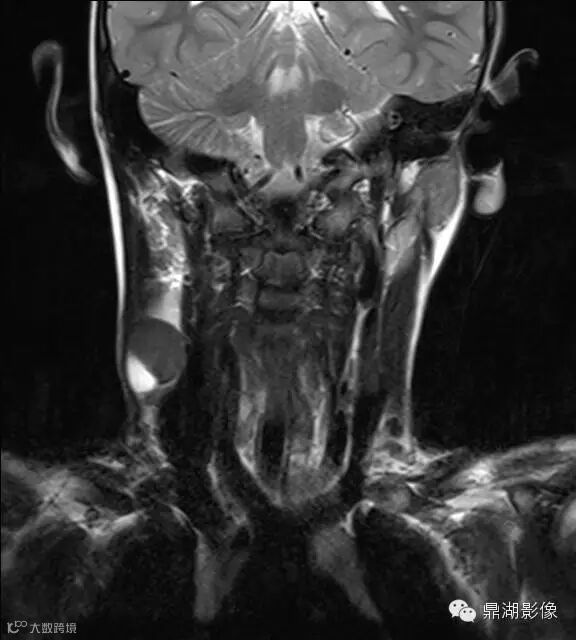

上海儿童医院韩燕乔教授诊断:考虑淋巴结炎 ,可见杯状分层,液液平

神经源性肿瘤:肿块较大,信号常不均,有人认为肿瘤位于屈肌的区域或伴有肌肉萎缩强烈提示神经源性肿瘤。

淋巴结核:多融合成团,呈花环状,边缘强化,淋巴结内见到斑点状钙化有助结核的诊断。

猫抓病性淋巴结炎:不少医生诊断为猫爪病,该病确实很接近。均为炎性改变,脓肿、坏死形成时,虽呈边缘强化特点,但多个淋巴结间界限清楚,无融合改变,内也无斑点状钙化。